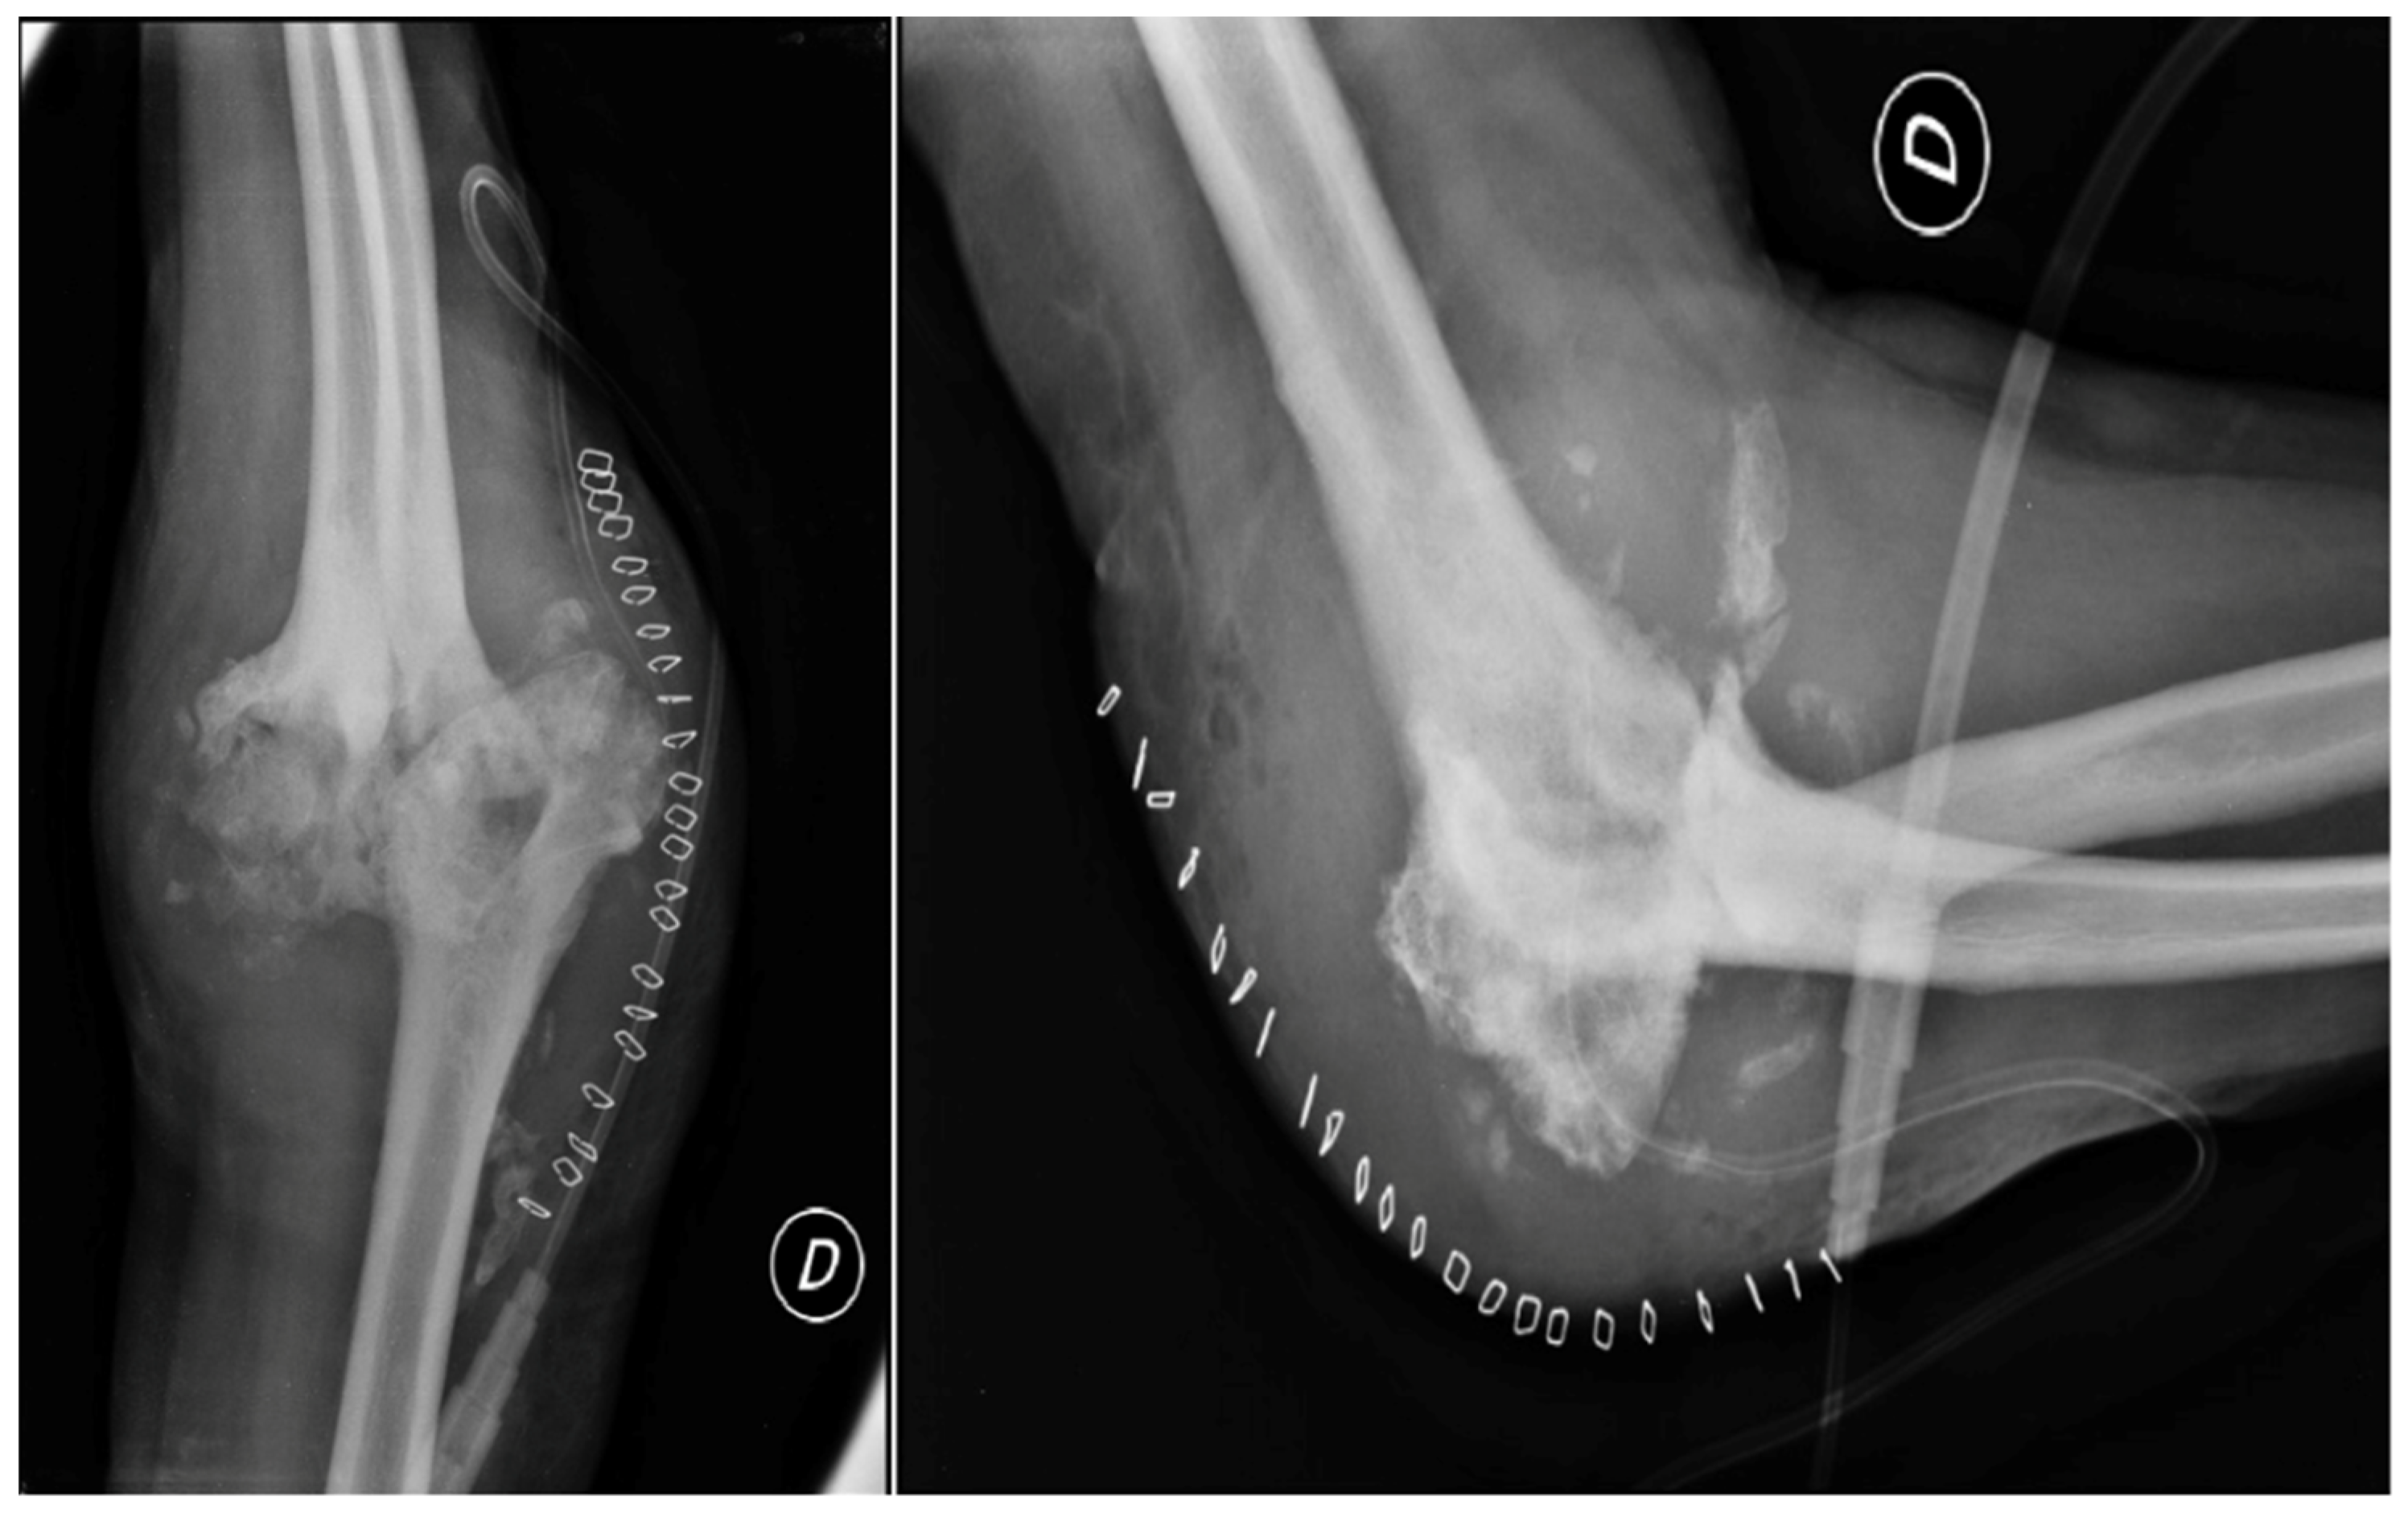

The patient had a good postoperative course, except for a small wound dehiscence with fibrinous serum secretions, which resolved in May 2014 with outpatient clinic treatments. In July 2014, after four months, the patient achieved complete extension and flexion of 100 degrees, with no significant changes in the X-ray findings. Two months later, in September 2014, the X-rays remained unchanged (Figure 9), and the patient had a flexion of about 105 degrees, complete extension and pronation, and limited supination of 5 degrees.

Figure 9. X-Ray anteroposterior, lateral in neutral position, in extension and in flexion views of the right elbow at 6 months after the second revision surgery.